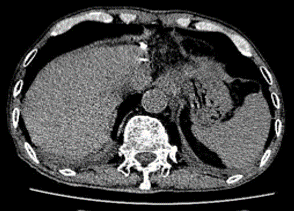

患者于2019年7月17日在我院肝胆外科于全麻下行左外叶肝切除+胆囊切除,手术顺利,术后予以抗炎补液、护胃制酸、保肝退黄、维持水电解质平衡、清洁换药等对症处理。

术后病理提示:送检部分肝组织一件,大小11cm×7.5cm×4cm,距肝切缘1cm见一大小4cm×3cm×2cm肿块;镜检为中分化腺癌伴坏死,组织学形态结合临床病史,考虑肠腺癌转移可能性较大。切缘未见癌;周围肝组织肝细胞轻度水肿、淤胆。慢性胆囊炎。